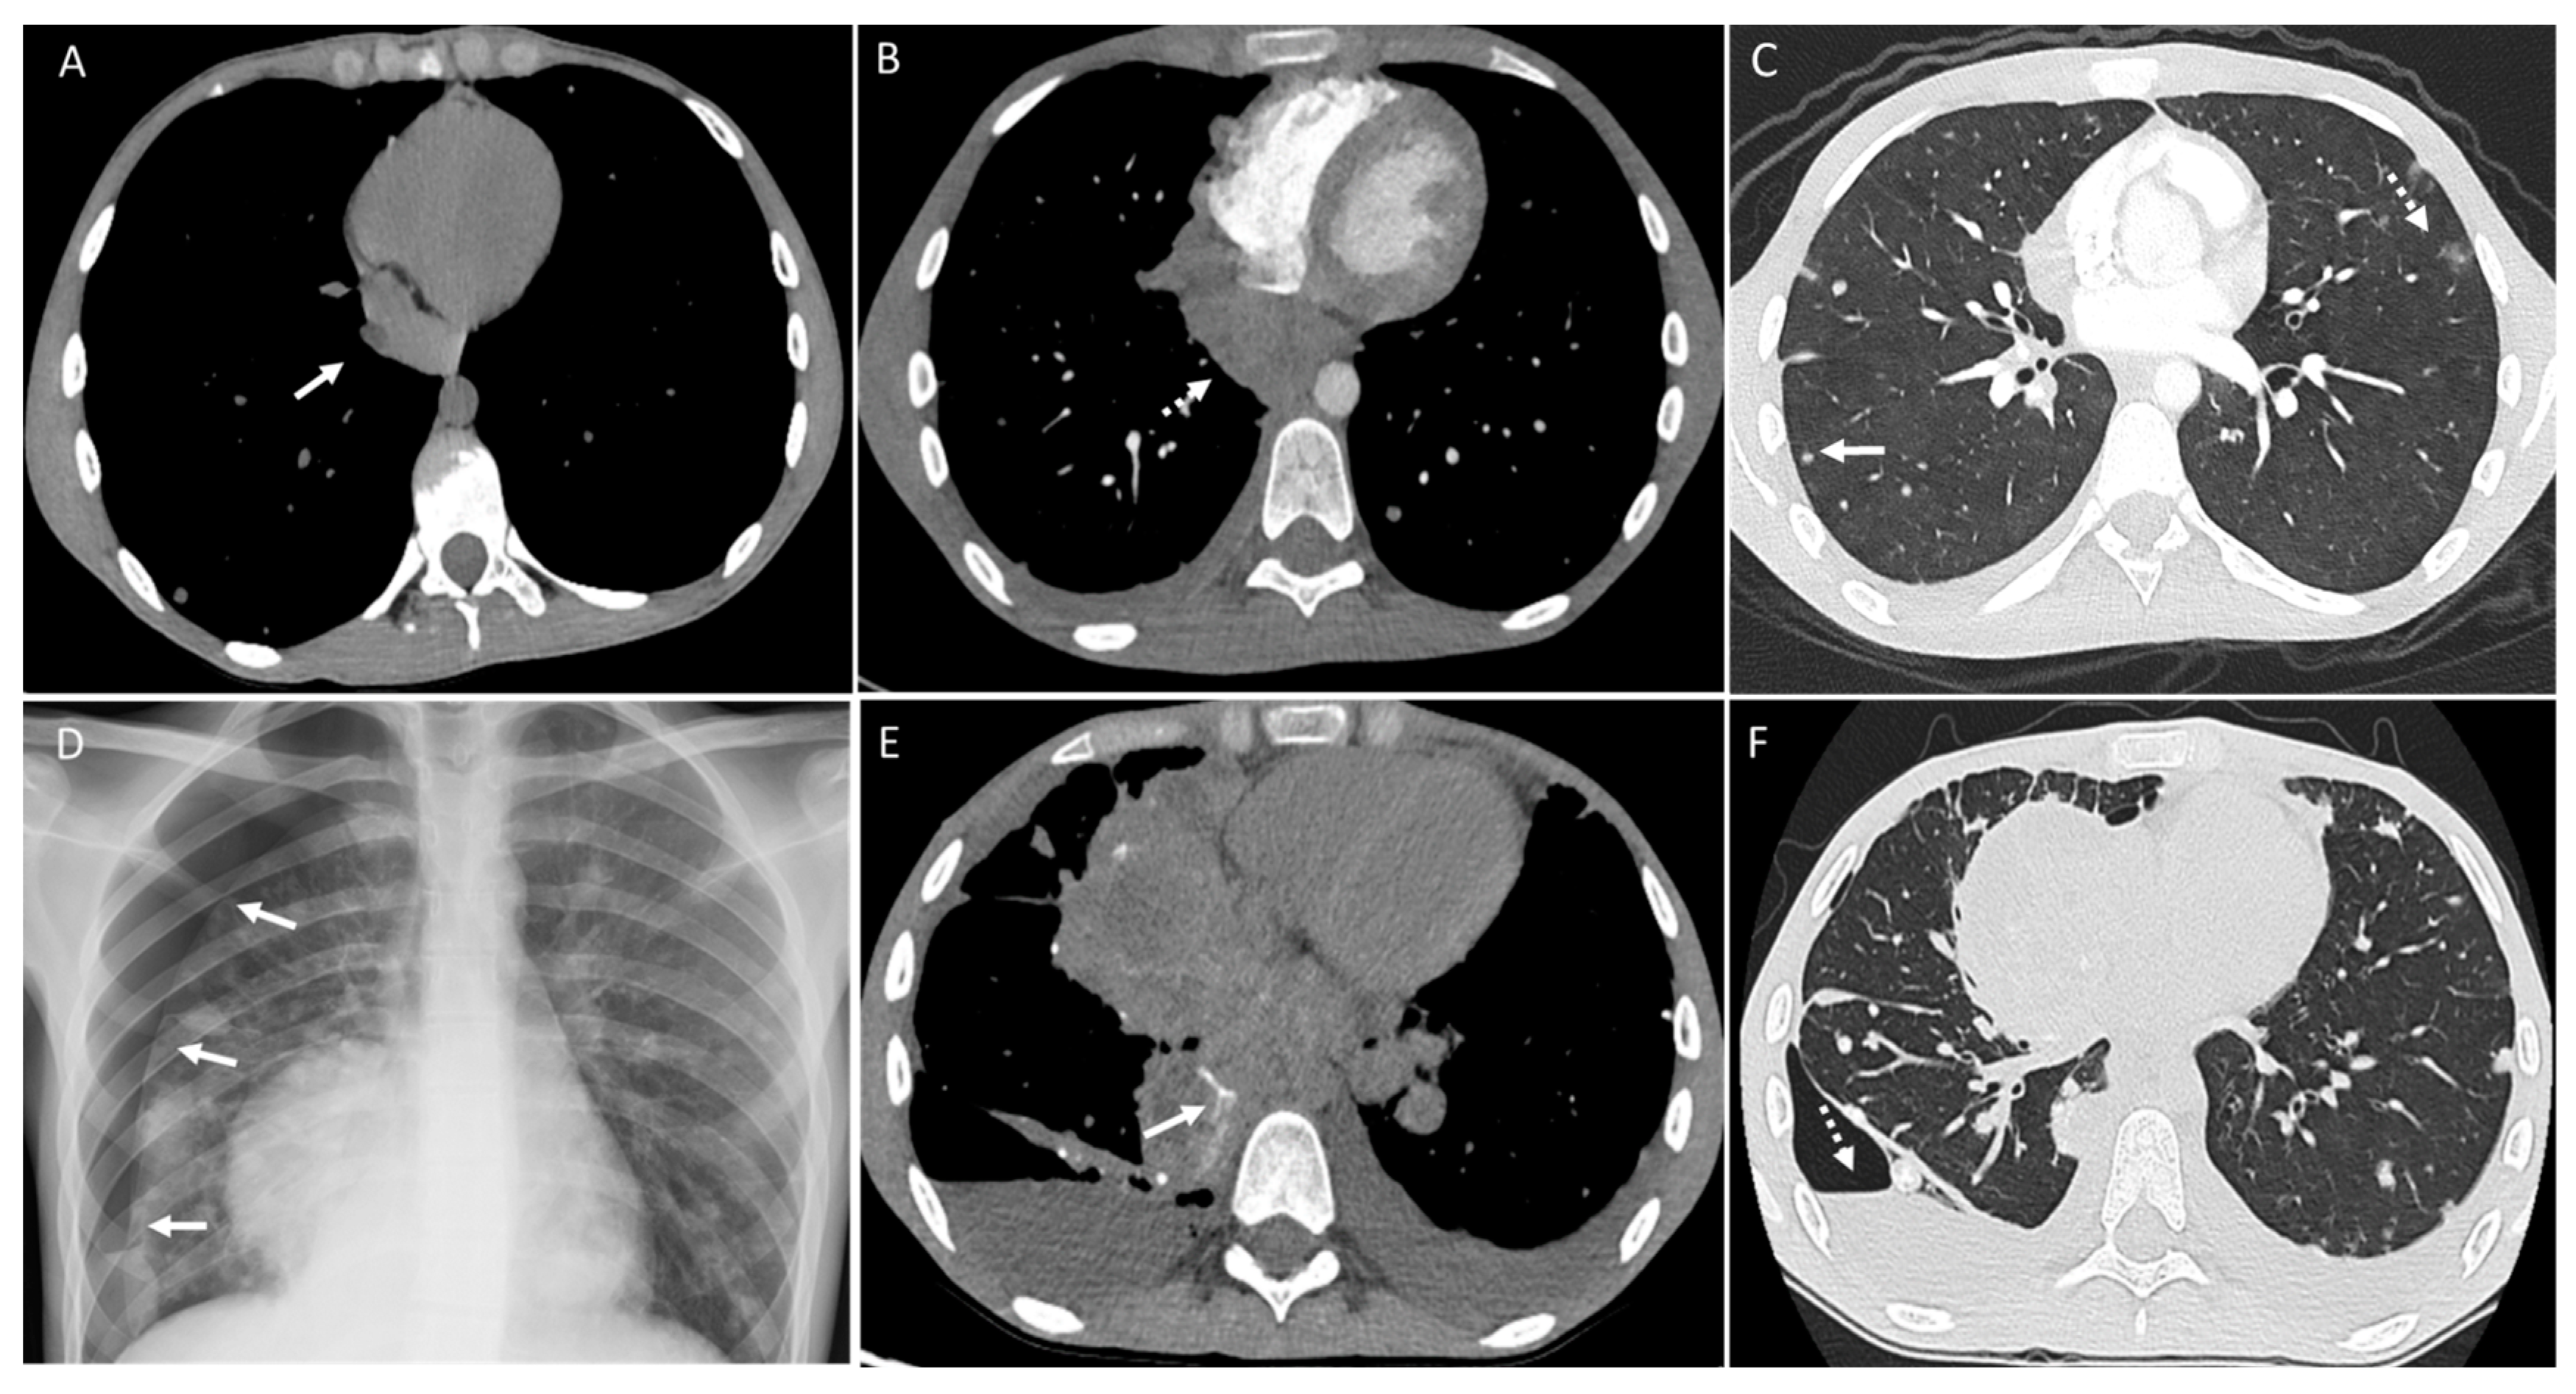

3. Pleura

4. Mediastinum and Hilum

5. Cardiac and Major Thoracic Vessels

6. Chest Wall